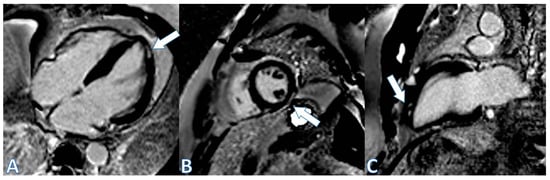

| CMR at hospitalization | LGE of both pericardial leaves and foci of late subepicardial enhancement on the basal inferolateral, lateral, and inferior walls | LGE at the level of the pericardial leaves and a basal inferolateral subepicardial focus | Edema and LGE in the lower-middle, inferolateral, and anterolateral segments | Edema and LGE at the anterolateral, basal-mid inferolateral and basal inferior segments, and intramyocardial in the mid-inferoseptal and apex segments |

| Control CMR at 3 months | Persistence of LGE on the inferolateral wall | Disappearance of LGE | - | - |

| Control CMR at 6–9 months | Persistence of LGE on the inferolateral wall | - | LGE in the inferolateral and anterolateral walls | LGE intramyocardial and subepicardial at inferolateral, anterolateral, and inferoseptal walls (reduced extent) |